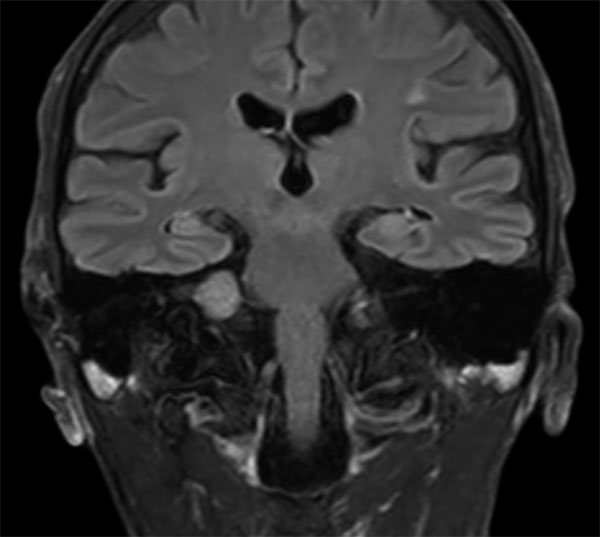

IAC – Acoustic Neuroma

Decreasing hearing of the right side. Buzzing and beating sensation in the right ear. Sometimes pain. Request for MRI of the inner ear without and with contrast agent.